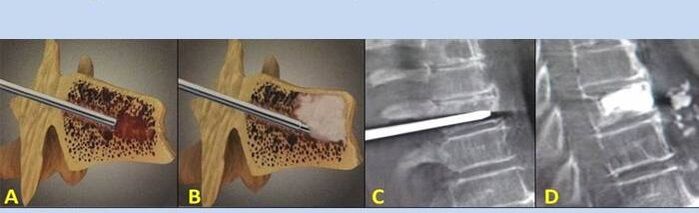

- Nucleoplastia – remoção do núcleo do disco intervertebral. A operação alivia a pressão nas terminações nervosas.

- Vertebroplastia por punção – método de estabilização das vértebras. Durante o procedimento, o médico preenche as cavidades da coluna com cimento ósseo.